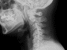

その為、ストレートを通り過ごし逆カーブになっていました。

それにより頭痛頻度も減ってきた傾向。週一回の治療で首の前弯(アーチ)が出来るまで約1月半。